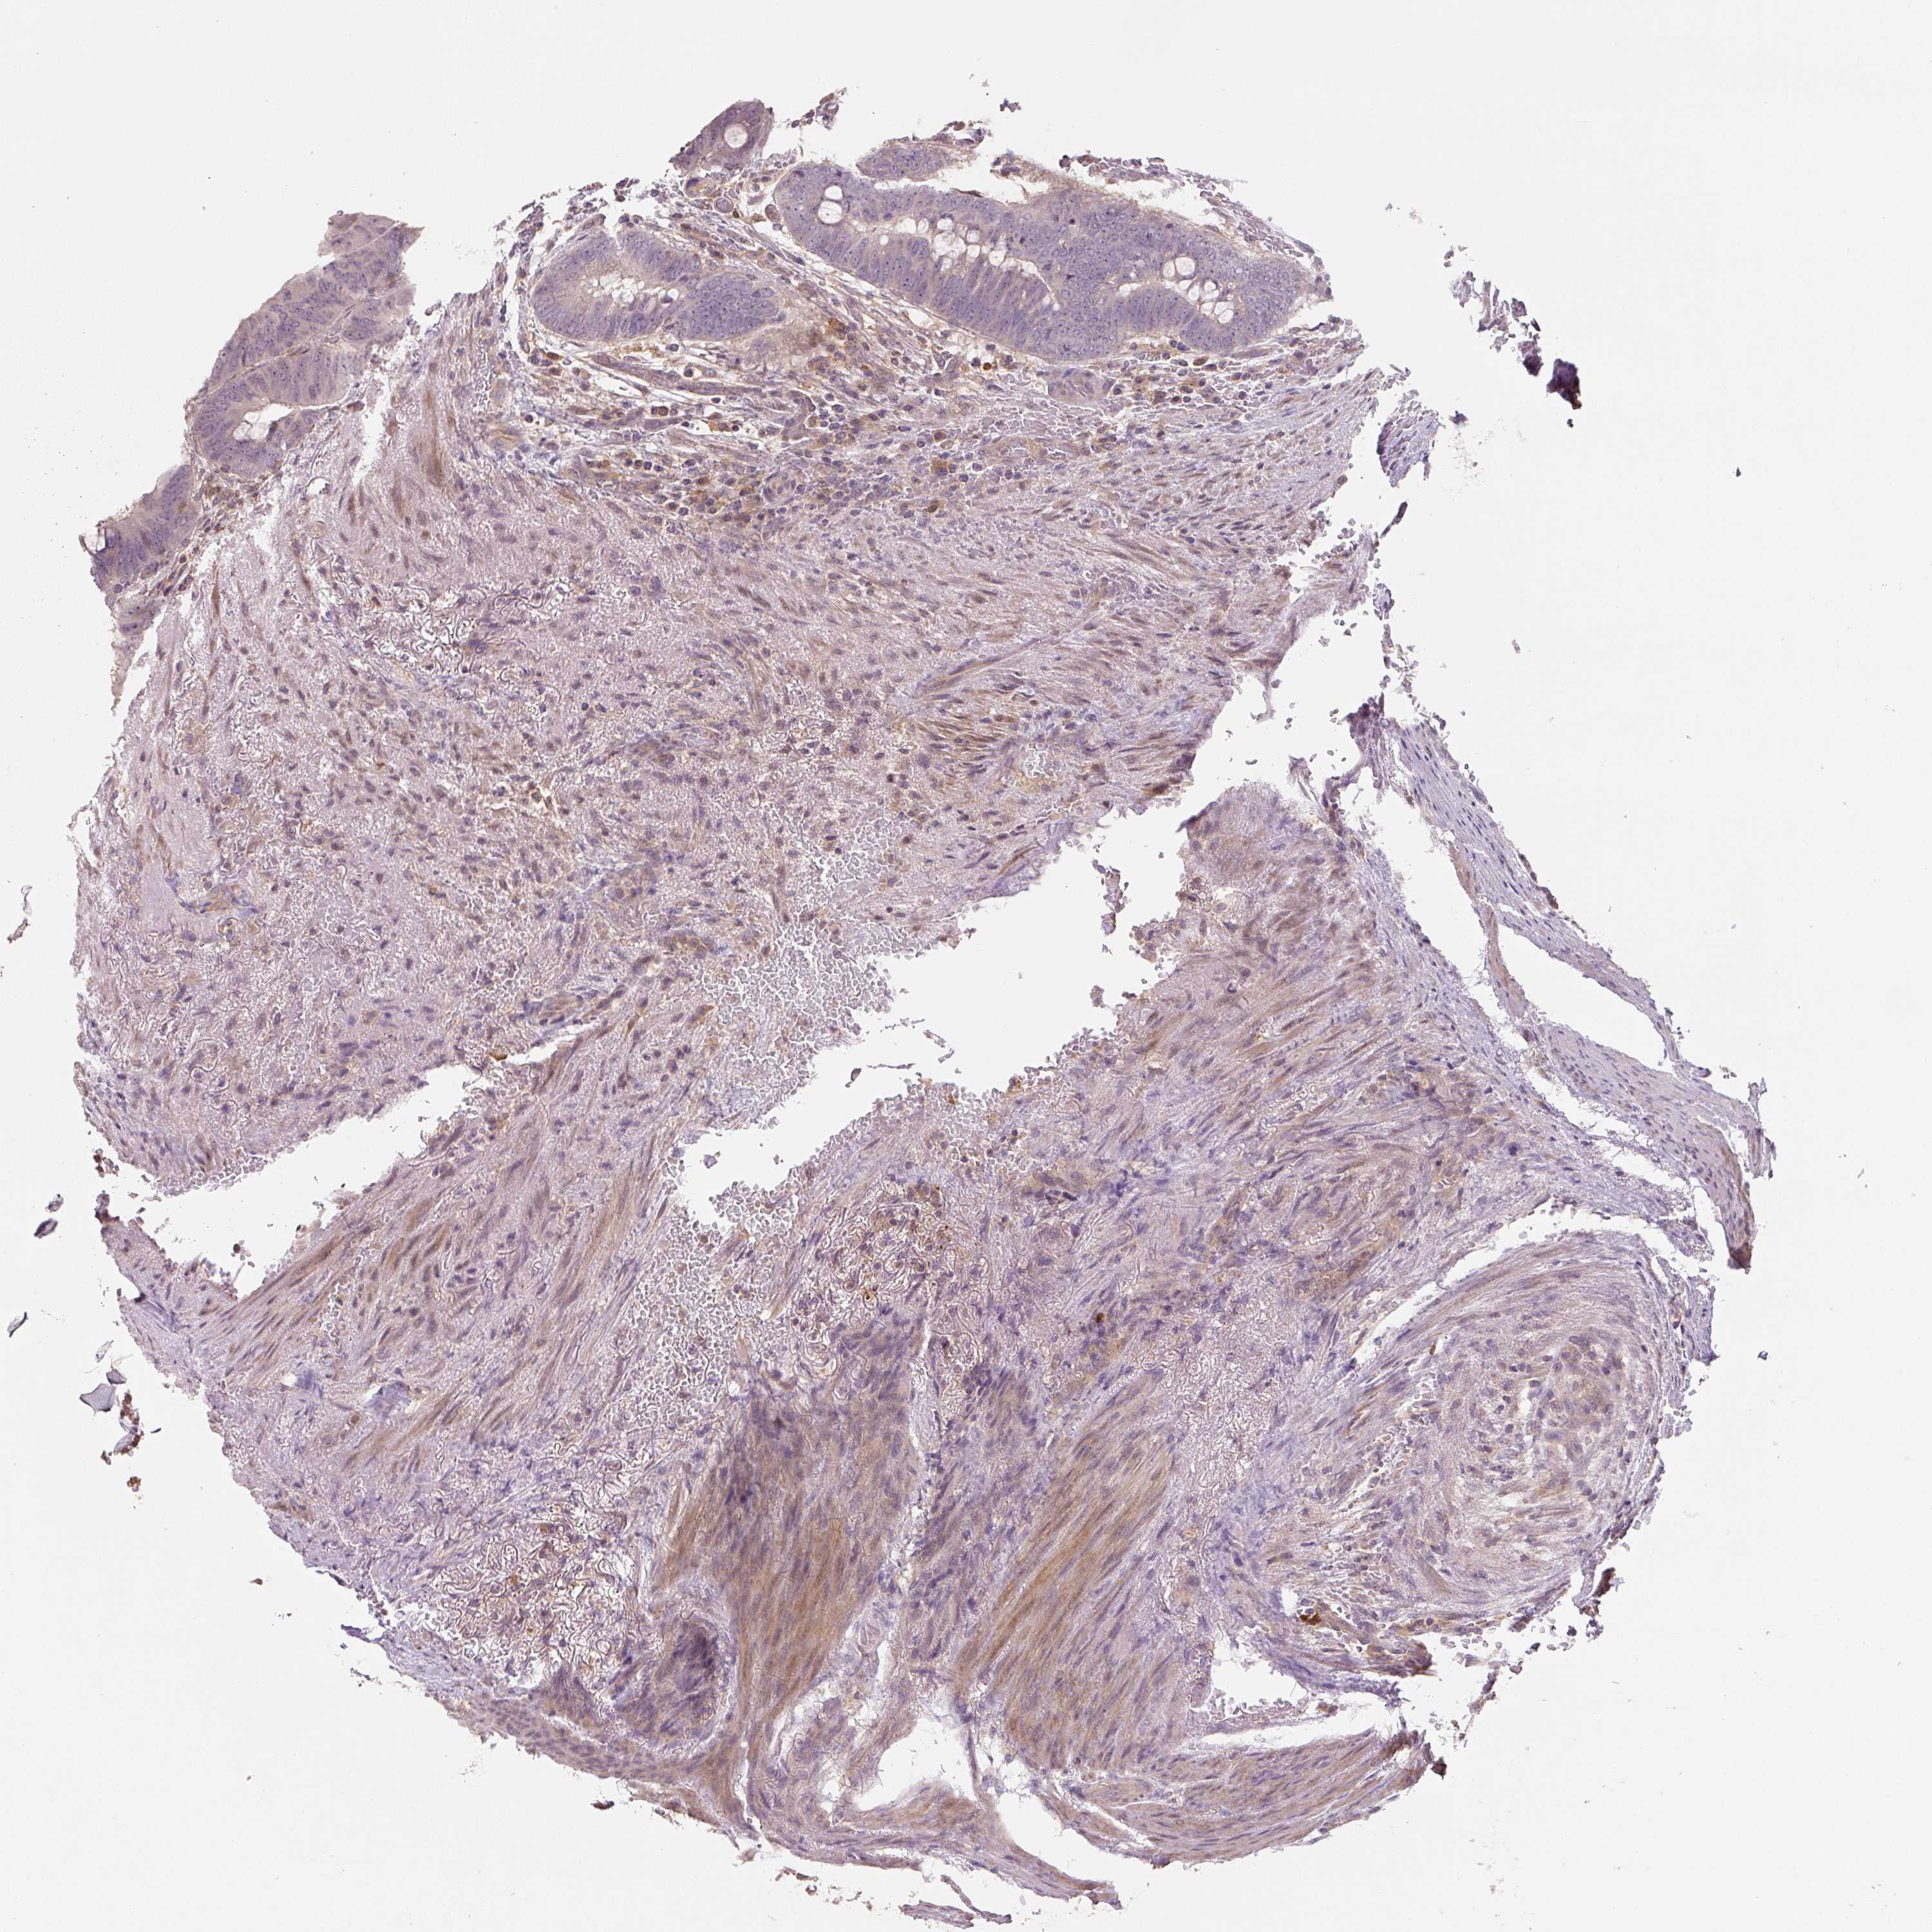

Colorectal cancer

Human cancer

Colon adenocarcinoma